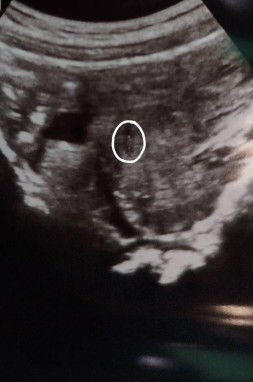

สวัสดีค่ะ พอดีอยากสอบถามแม่ๆค่ะ พอดีเป็นท้องแรกตอนนี้อายุครรภ์6วีคแล้วค่ะ แต่ไปซาวครั้งแรกตอน5วีค5วัน คุณหมอบอกเจอถุงแล้ว มีรกมีตัวอ่อนแล้ว อยากทราบว่าแม่ๆท่านอื่นมีใครเจอน้องไวบ้างไหมคะ พอดีจะไปฝากท้องวันที่3นี้แล้วค่ะคุณหมออีกคลีนิคพึ้งนัดค่ะ ในรูปใบซาวที่วงไว้คือตัวน้องที่คุณหมอบอกค่ะ #ขอบคุณล่วงหน้าสำหรับความคิดเห็นค่ะ #ขอคำแนะนำกับแม่ๆด้วยนะคะ #ท้องแรก